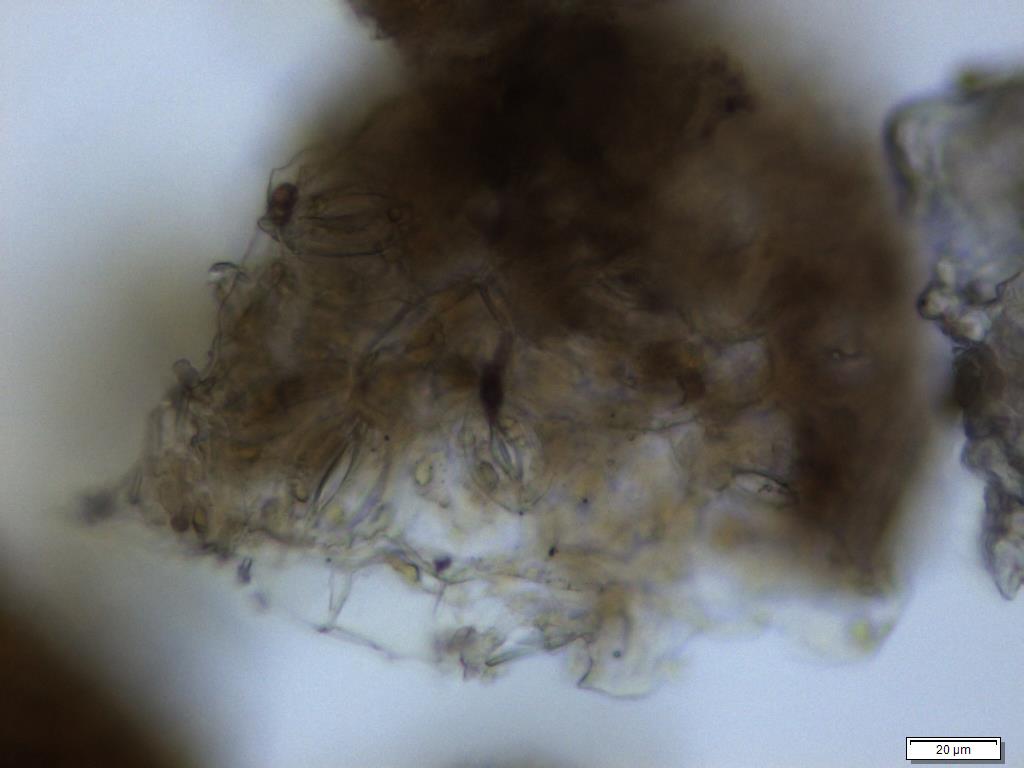

Microscopy

Powdered material consists of fragment of adaxial epidermis cell with straight to wavy anticlinal wall; abaxial epidermis cell with stomata; fragment of parenchyma cell; fragment of vessels (i.e. spiral, spiral with thickening and scalariform vessel); fragment of fibre and a group of acicular calcium oxalate crystal [ 7 ].

Figure 2 : Microscopic characters of Morinda citrifolia leaves powder of 0.355 mm size. (a) Adaxial epidermis cells (magnification 20x); (b) parenchyma cells (magnification 40x); (c) stomata cells (magnification 20x); (d) spiral vessel (magnification 20x); (e) scalariform vessel (magnification 40x); (f) spiral thickening vessel (magnification 40x); (g) fragment of scalariform and spiral thickening vessels (magnification 20x); (h) fibres (magnification 40x); (i) acicular crystal (magnification 40x). [Scale bars: a = 20 µm; b = 10 µm; c = 20 µm; d = 20 µm; e = 10 µm; f = 10 µm; g = 20 µm; h = 10 µm; i = 10 µm]